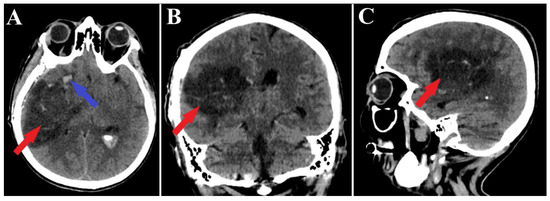

A follow-up non-contrast CT scan displayed a region of deep right fronto-temporal hypodensity, indicative of a post-surgical sequelae (Figure 4). Additionally, the CT scan identified areas of hemorrhage, which were deemed not to require further surgical intervention (Figure 5). Subsequent control angiography of the right carotid artery confirmed the complete excision of the AVM, with the preservation of the pathway of the right anterior choroidal artery (Figure 6). The patient was then managed with conservative treatment, resulting in a favorable clinical progression and substantial neurological improvement. After 2 weeks of hospitalization, at the time of discharge, the patient’s left hemiparesis had improved to 3/5 on the Medical Research Council (MRC) scale and assigned GCS was 12 points (eye response—3 points, verbal response—4 points, motor response—5 points).

Figure 4.

Postoperative CT scan, malformation resection shown. All three sections of the CT scan (A—axial section, B—frontal section, C—sagittal section) indicate a total resection of the arteriovenous malformation (red arrows), and the axial section of CT scan (A) depicts a small portion of an intraparenchymal hematoma (blue arrow).

Figure 5.

Postoperative CT scan, hematoma. Those images (A—axial section, B—frontal section, C—sagittal section) show a persistent pan ventricular and intraparenchymal hematoma (red arrow), as well as the contralateral intraventricular infiltration of the hematoma (blue arrows).